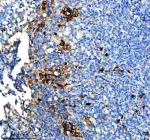

Immunohistochemical staining of CD163b/CD163L1 using anti-CD163L1 antibody. CD163L1 was detected in a paraffin-embedded section of human tonsil tissue. Heat mediated antigen retrieval was performed in EDTA buffer (pH 8.0, epitope retrieval solution). The tissue section was blocked with 10% goat serum. The tissue section was then incubated with a dilution of 1:50 rabbit anti-CD163L1 antibody overnight at 4oC. Peroxidase Conjugated Goat Anti-rabbit IgG was used as secondary antibody and incubated for 30 minutes at 37oC. The tissue section was developed using an HRP secondary and DAB substrate.